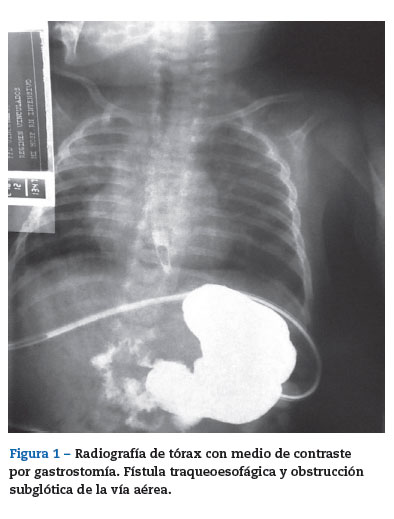

El 20 de enero fue llevado a cirugía, ingresó a salas de cirugía con oxígeno suplementario, se colocó en cuna de calor radiante y se monitorizó. Signos vitales iniciales: frecuencia cardiaca 147 latidos/min, frecuencia respiratoria 27 respiraciones/min, presión arterial 95/47 mmHg y saturación arterial de oxígeno 91%. Se realizó inducción inhalatoria con sevoflurano y se canalizó la vena periférica del miembro superior derecho con catéter intravenoso nómero 22. A la inducción inhalatoria con sevoflurano se adicionaron 15 mg de propofol (4mg/kg), 15 [xg de remifentanilo (4[xg/kg) y 2 mg de rocuronio (0,5 mg/kg). Ventilación fácil con mascara facial. Se realizó laringoscopia directa con hoja recta #1, visualizándose adecuadamente la glotis, se intentó pasar tubo #4,0 sin neumotaponador sin lograr avance más allá de las cuerdas vocales; se realizaron intentos adicionales con tubos #3,5, 3,0 y 2,5, sin lograr intubar la tráquea. Entre los diferentes intentos el paciente fue ventilado con máscara facial, manteniendo la saturación de oxígeno siempre por encima del 90%. Se solicitó asistencia a otro anestesiólogo, pero no fue posible intubar al paciente. En las placas de tórax (fig. 1) se observaba una obstrucción subglótica severa, por lo cual se decidió colocar una máscara laríngea #1,0 (fig. 2), lográndose un adecuado sello de la vía aérea (mediante la valoración clínica de la ventilación manual) con ventilación simétrica y capnografía positiva. Se pasó a ventilación mecánica controlada por presión con presión inspiratoria máxima de 18cmH20, frecuencia respiratoria de 18 respiraciones/min, relación inspiración espiración de 1:2. Se colocó analgesia caudal y se inició cirugía. Durante el procedimiento se mantuvo la saturación de oxígeno y el CO2 espirado dentro de lo normal: 96% y 34mmHg, respectivamente (fig. 3). Duración total de la cirugía: 2,5 h, sin complicaciones. El paciente fue trasladado a la UCIN con la máscara laríngea y con respiración espontánea. Se entregó en la UCIN estable, sin dificultad respiratoria y con adecuada oxigenación (96%); 10 min después le retiraron la máscara laríngea y le pusieron nuevamente cánula nasal. El paciente evolucionó satisfactoriamente,saliendo de la UCIN a cuidados básicos al siguiente día del procedimiento.